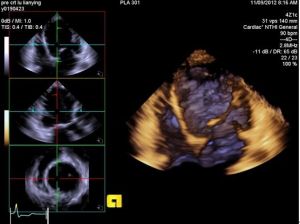

3.超聲心動圖:心尖四腔可見心臟增大而以左心室擴大為顯著,左室室壁運動瀰漫性減弱;如有附壁血栓則多發生在左室心尖部;多合併有二尖瓣和三尖瓣反流。測定射血分數和左室內徑縮短率可反映心室收縮功能。室壁運動節段性異常需要與缺血性心肌病鑑別,將超聲心動圖檢查與多巴酚丁胺負荷實驗相結合有助於鑑別。下圖為擴張型心肌病的三維超聲心動圖圖像。4.冠脈造影檢查:存在胸痛的DCM患者需要作冠脈造影或冠脈CTA檢測,有助於與冠心病鑑別。左心室造影提示心室腔擴大,可見整體性的室壁運動減弱。